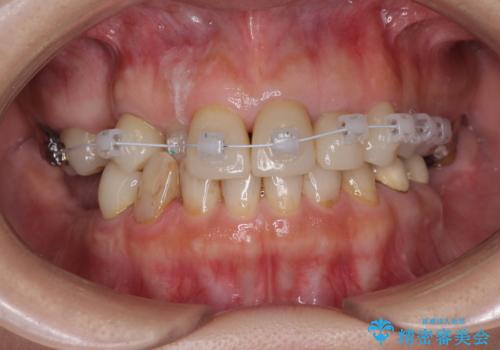

①仮歯を装着

②矯正治療

上顎の前歯はガタガタがあり、過去に治療した歯はつぎはぎのようになっており、審美的に周囲と調和がとれていない状態でした。

セラミックのかぶせ物だけで、歯並びまで変えようとするのには限界があります。